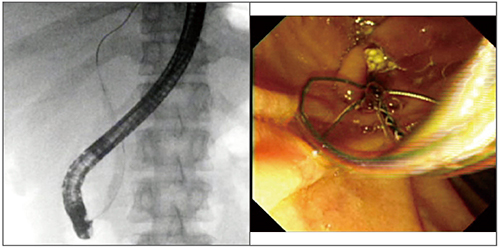

最後に、嵌頓結石について触れたい(図17)。嵌頓結石に対しては、ガイドワイヤ越しに行うことが有用である。ガイドワイヤがうまく奥まで入った場合には、必ず先端チップが細いバスケットあるいはバルーンを用いることで、安全に採石できる(図18)。また、POCSも有用なほか、当科では、レーザーあるいはEHLも実施することが多い。肝内胆管迷入嵌頓結石に対しては、パピロトーム(ナイフ)の刃を振って結石を肝外胆管まで移動させる方法もある(図19)。本症例は、そのままナイフで取り出したが、ナイフから結石を外し、バスケットで採石する方法もある。

図18 ガイドワイヤ誘導式バスケットによる結石嵌頓予防

a:ガイドワイヤを奥まで挿入

b:結石が排出された